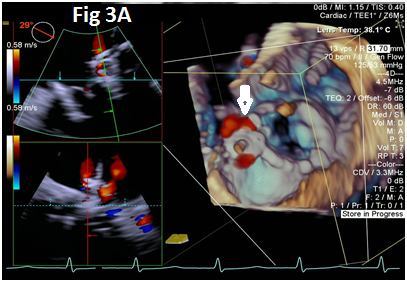

A 73-year-old female with mechanical mitral valve, tricuspid annuloplasty (32mm Edwards Physio Tricuspid incomplete ring) underwent Transcatheter Tricuspid Valve Replacement (TTVR) using off-label 29mm Edwards Sapien 3 (S3) Transcatheter Heart Valve (THV). Immediate post valve deployment, mild Perivalvular Leak (PVL) was noticed at the septal aspect (area of incomplete annuloplasty ring). Eighteen months later, patient presented with recurrent right heart failure and paracentesis due to severe tricuspid PVL (Figure 1A-C, Video 1). Percutaneous PVL closure under general anesthesia, Trans-esophageal Echocardiography (TEE) was performed. Via femoral venous access, defect was easily crossed with Agilis steerable sheath, multipurpose catheter and 0.035” glide wire. Despite recurrent attempts, wire came through the PVL but then traversed through open cells of S3 into the right ventricle (Figure 2A), confirmed with Armada 6mm balloon waist at the S3 cage (Figure 2B) (despite inflating 28mm Z med balloon inside S3 cage, Figure 2C). We decided to partially deploy the plug and assess valve function. Using 7.5F Asahi Eaucath multipurpose guide, a 12mm AmplatzerTM Vascular plug II (AVP II) was advanced through the defect. The ventricular disc was opened inside the S3 cage while body in the PVL defect (outside the S3 cage) and atrial disc on the atrial side of PVL (Figure 3A-B). With S3 function unaffected, no central leak and minimal gradient, PVL reduced to mild severity (Figure 4A-D, Video 2); the AVP II was successfully deployed (Figure 5). At 3-month follow up, there was an excellent symptomatic improvement (NYHA functional class I), with no heart failure re-hospitalization or paracentesis. Deployment of plug disc inside the valve frame is not recommended due to fear of interference with leaflet function and possible injury in long term. There was no immediate issue with the valve function in this case (due to space between the leaflet and frame of S3 and depends on size of plug used). Valve-in-Valve (S3-in-S3) would have certainly sealed all open cells treating this PVL but is more expensive option.

Figure 3 Successful implantation of AmplatzerTM Vascular plug II (white arrows).

Figure 4 Post AmplatzerTM vascular plug II with mild residual PVL (4A), mildly elevated trans-S3 gradient (4B) and normal leaflet mobility of S3 (diastole 4C, Systole 4D).